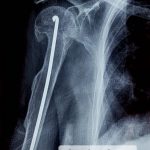

El IGSS brinda atención médica a niños con padecimientos de “huesos de cristal”

EL IGSS brinda atención médica a niños con padecimientos de “huesos de cristal” 2-2